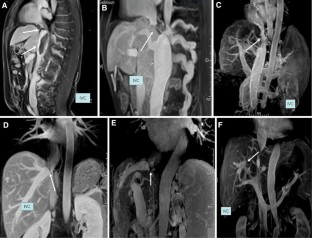

We retrospectively compared MRI results of 24 patients with acute and 82 patients with chronic BCS using Mann–Whitney U test for ascites volume, and Fisher’s exact test for intrahepatic venous collaterals and extra-hepatic venous collaterals. In the acute group, MRI findings suggested thrombosis in hepatic vein (HV) in all acute patients and additional inferior vena cava (IVC) thrombosis in 5 patients. In the chronic BCS group, 6 and 15 patients showed solitary obstruction either in the IVC or HV, respectively, while 61 patients showed combined IVC and HV obstruction. More patients with acute BCS presented with ascites accompanied with high signals on T2WI from intravenous obstructive lesions. Further, the average maximal spleen diameter in patients with acute BCS, and the ratio of patients with acute BCS developing intrahepatic venous collaterals and extra-hepatic venous collaterals were also lower compared with chronic BCS. All these differences were statistically significant.

Fig. 1